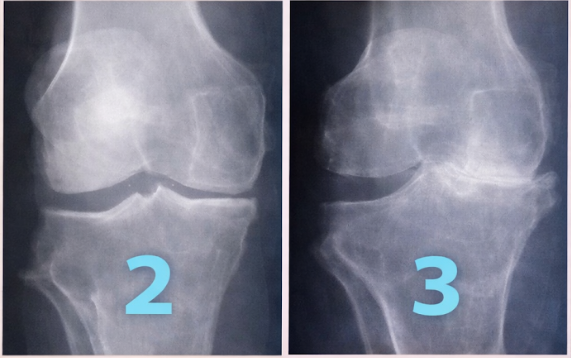

¿Tu rodilla se ve asi?

La degeneración avanza por 4 grados, no dejes que tu rodilla llegue a su ultima instancia donde la única solución es el reemplazo con PROTESIS DE RODILLA